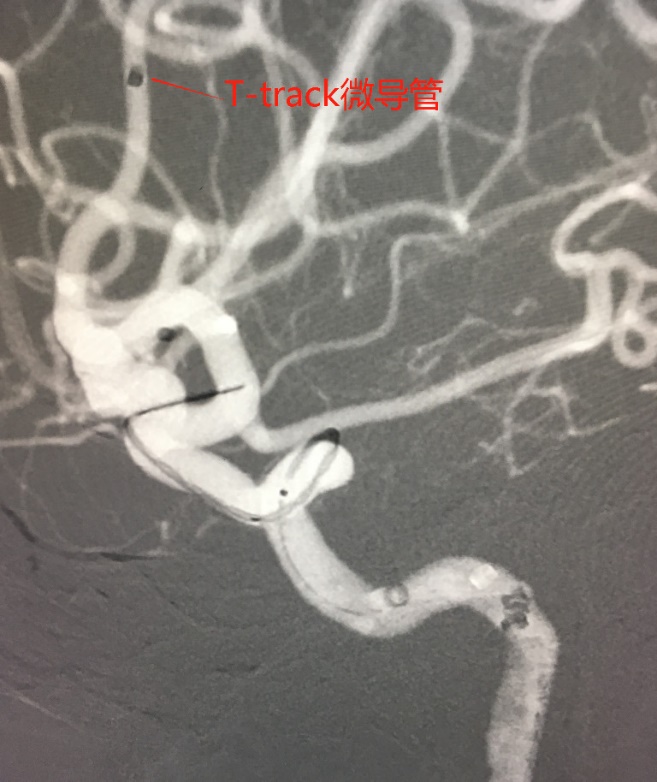

麻醉成功后,患者仰卧,常规消毒,铺巾, Seldinger法穿刺右侧股动脉,置入5F动脉鞘,置入5F造影管行右侧颈内动脉正侧位及3D造影后,更换6F长动脉鞘,6F中间导管在导丝引导下进入右侧颈动脉分叉端并固定。根据3D造影选择工作体位并放大做路图后,T-track微导管在微导丝引导下进入右侧大脑中动脉,经微导管送入4.0×45mm Tubridge®支架,观察 Marker位置后,于颈动脉分叉附近缓慢释放支架。

Tubridge®释放过程

锚定后,整体回撤至合适位置后,通过张力释放法缓慢释放支架,直至支架完全打开。观察见支架贴壁良好,动脉瘤颈完全覆盖,遂完全释放支架。